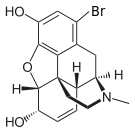

Halogenated morphine derivatives

- 1-Bromocodeine

- 1-Chlorocodeine

- 1-Iodomorphine

Structures

| Other open chain opioids | ||||

|---|---|---|---|---|

1-Bromocodeine |

1-Chlorocodeine |

| ||